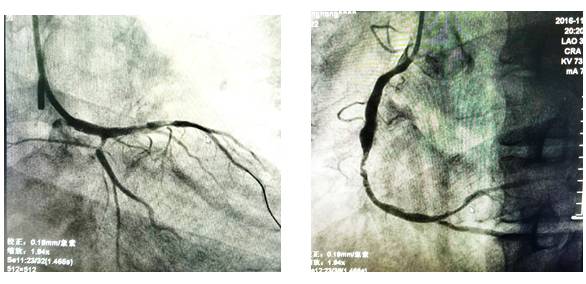

19:37造影:严重的左主干病变!

19:53 开始PCI

20:06 球扩后植入1枚支架

20:16 最后结果